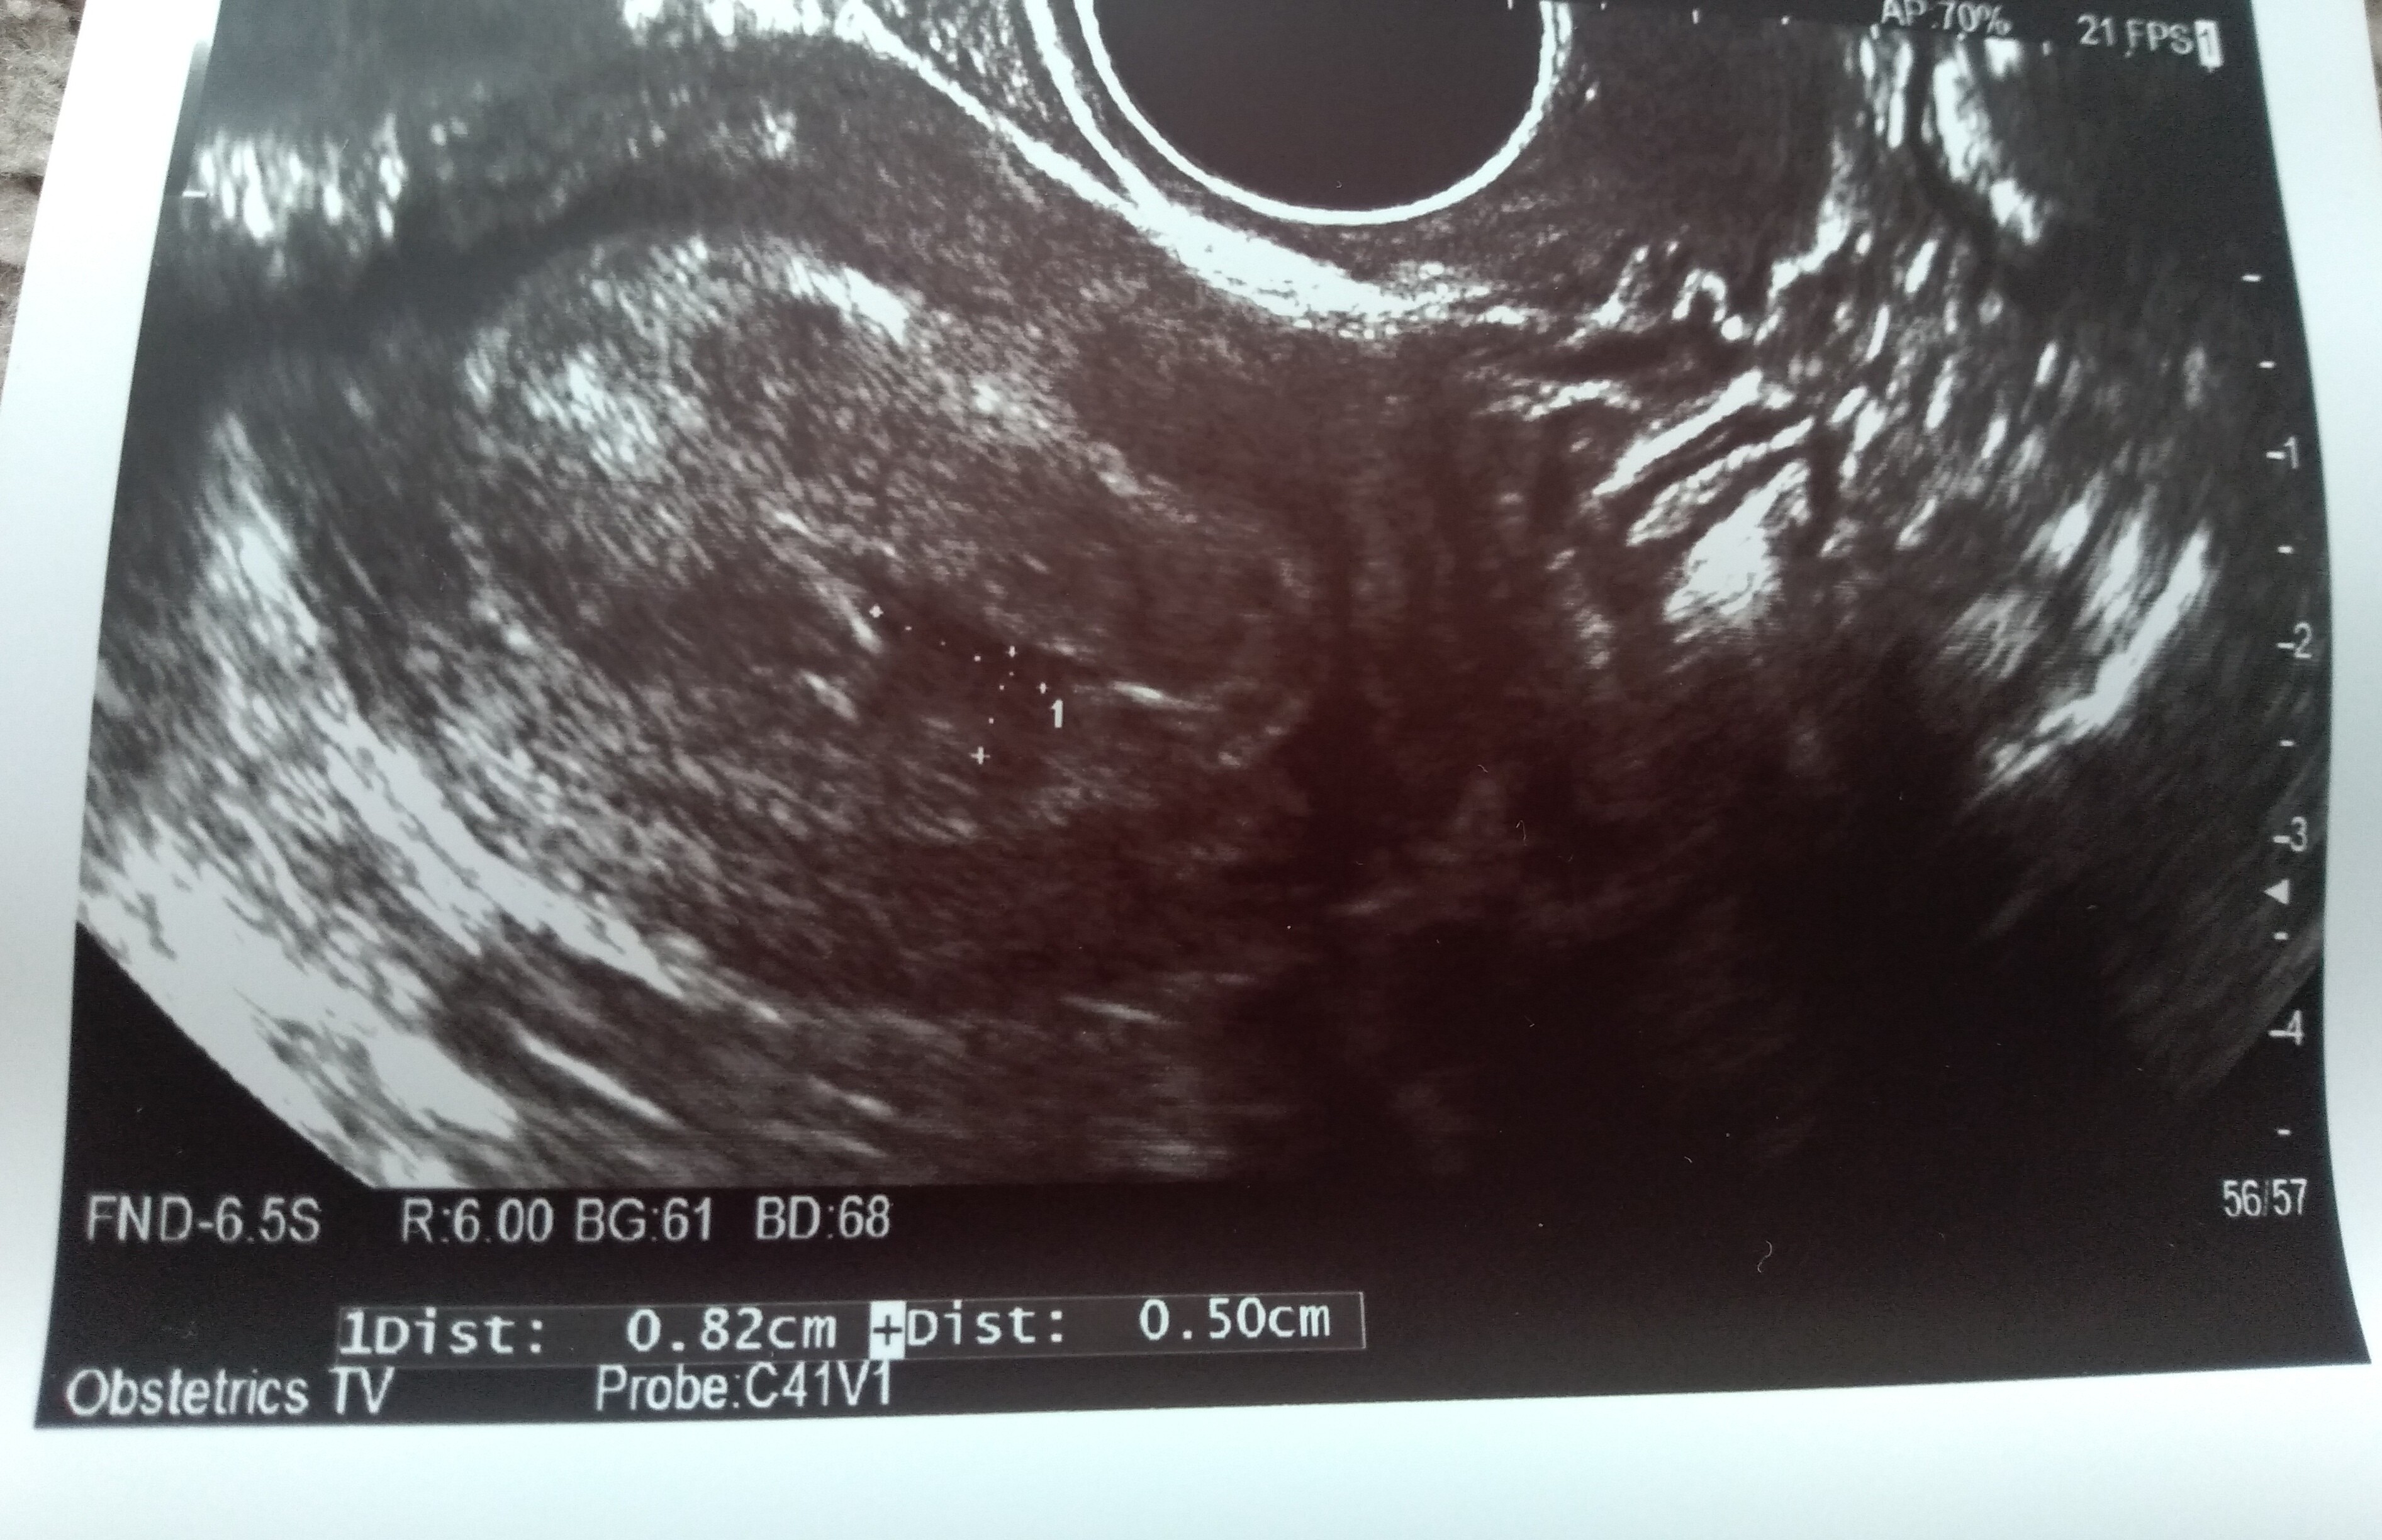

Ja w sumie sama nie wiem jaka wielkość bo lekarka mówiła 8 na 5 mm. Mówiła, że mam parę krwiaków w sumie. Ale na zdjęciu jest też coś na 2,7cm na 1,9 cm. Tylko z tego wszystkiego już sama nie wiem co. Czy to krwiak czy co. Pokaże Ci zdjęcia. Zobacz które u Ciebie podobnie wyglądało?Nie mam zdjęcia, ale z tego co widziałam na ekranie to ok 3 cm na 2,5 cm. Lekarz określił go jako nadkosmówkowego ale w internatach jest mowa tylko o podkosmówkowych. Na razie jestem w szpitalu na obserwacji, wiec zobaczymy. Ale jest też jasna strona medalu, wg OM 7 + 4 i to samo z usg. W poprzednich ciążach nie widziałam serduszka a tu było, wiec leżenie mi nie straszne nawet do końca, oby tylko z dzidzia było wszystko ok ❤